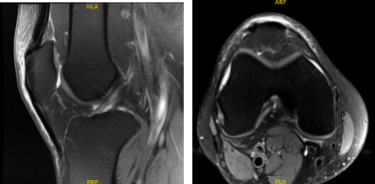

The patient presented MRI results that showed mild to moderate insertional quadriceps and proximal patellar tendinosis. There is prominent spurring along the inferior pole of the patella without a separate ossific fragment or surrounding bone marrow edema indicative of previous traction injury.

No meniscal tear or ligament injury. Cartilage is preserved. For the right knee, the X Ray results have shown Shallow undersurface tear at the posterior horn/body junction of the medial meniscus and undersurface fraying of the posterior horn.

MRI-3T Left Knee non-contrast

MRI-3t Right Knee non-contrast